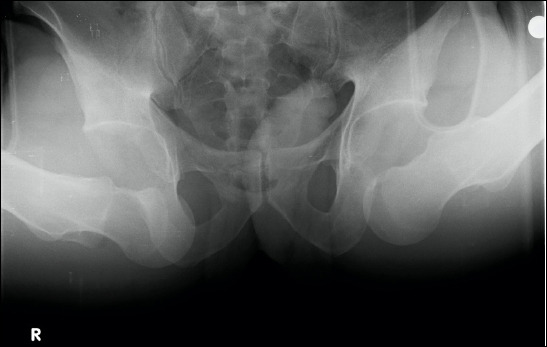

Bilateral obturator hip dislocations are quite rare injuries. This case report presents a 27-year-old male patient who experienced bilateral obturator hip dislocation due to a falling concrete electric pole. The unique features of this case include the unusual mechanism of injury and the absence of associated fractures, which differentiate it from other cases reported in the literature. Locked hip position and the presence of head trauma were discussed as factors that could delay treatment. Hip dislocations could be reduced within the first two hours. During a follow-up period of two years, the patient showed no signs of avascular necrosis or osteoarthritis and reported no clinical complaints. Bilateral obturator hip dislocations are quite rare injuries. This case report presents a 27-year-old male patient who experienced bilateral obturator hip dislocation due to a falling concrete electric pole. The unique features of this case include the unusual mechanism of injury and the absence of associated fractures, which differentiate it from other cases reported in the literature. Locked hip position and the presence of head trauma were discussed as factors that could delay treatment. Hip dislocations could be reduced within the first two hours. During a follow-up period of two years, the patient showed no signs of avascular necrosis or osteoarthritis and reported no clinical complaints.